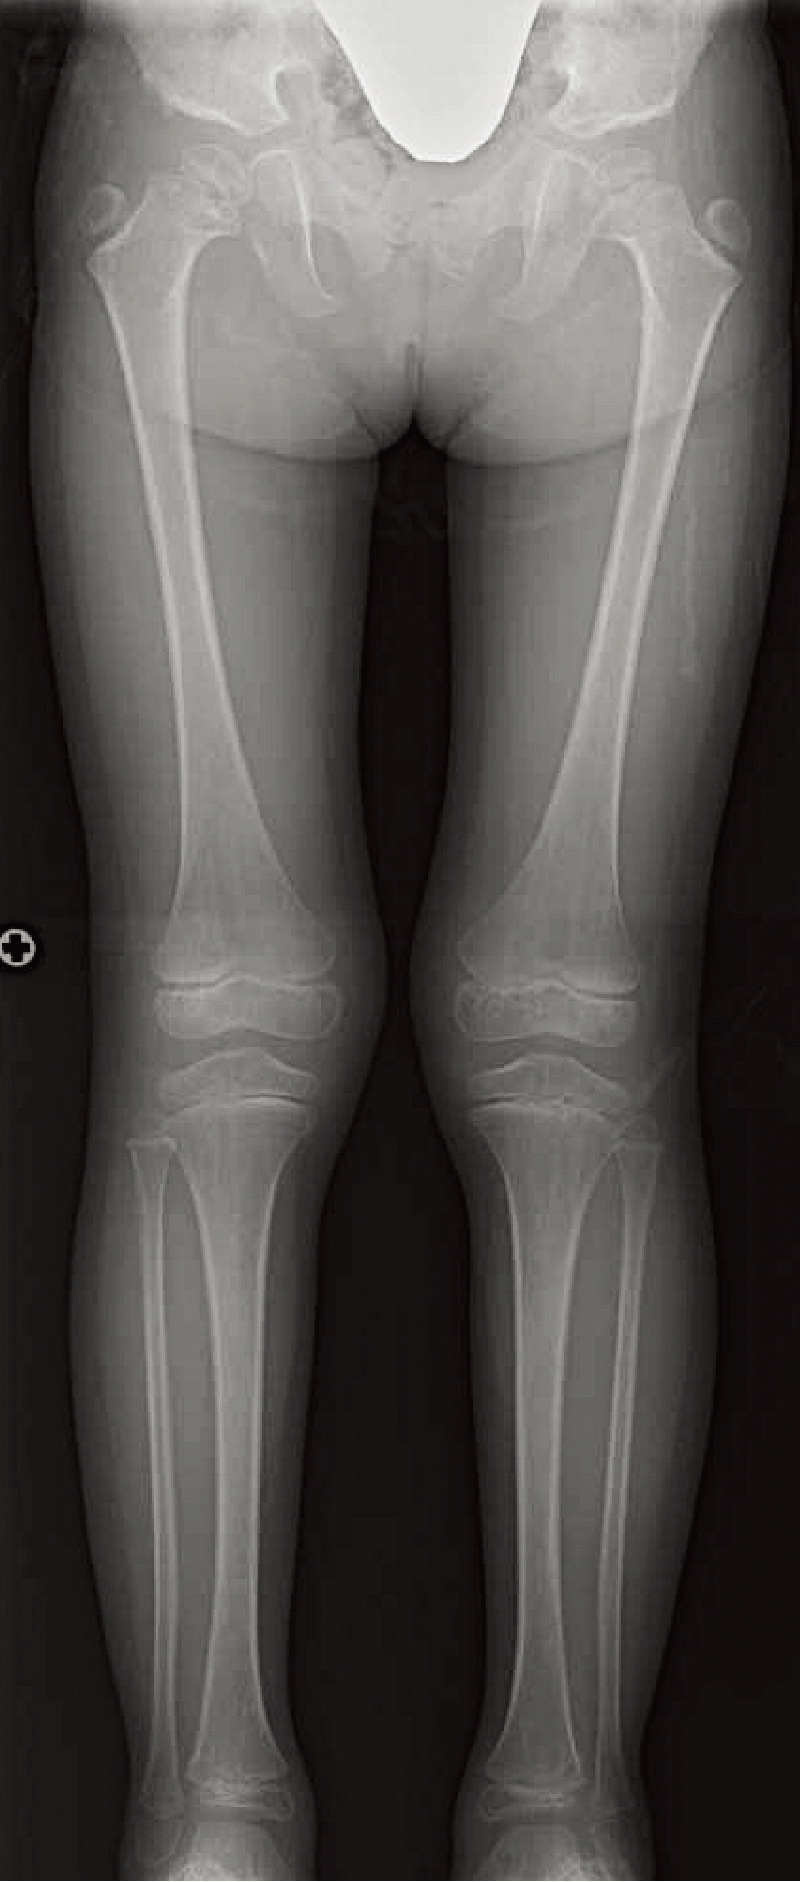

A. 背面像(6歳、女):内反膝を伴った体幹短縮型低身長。

B. 両下肢正面像(6歳、女):著明な内反膝および、大腿骨頭骨端核や膝周囲の骨端核の骨化遅延を認める。